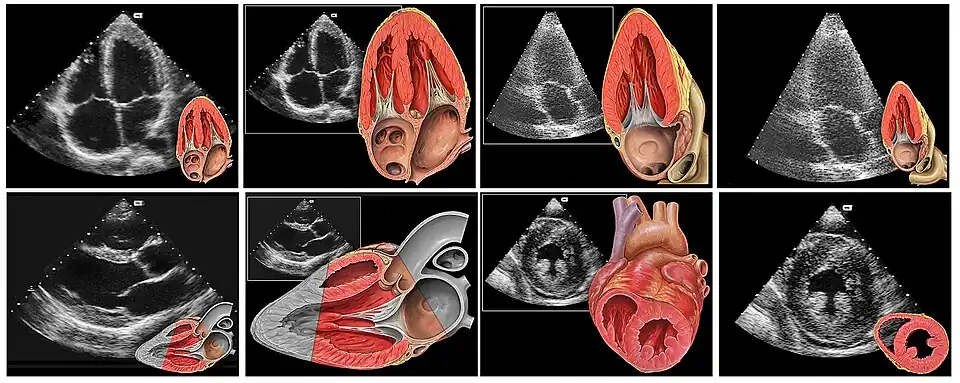

Bei der Transthorakalen Echokardiografie (TTE) wird das Herz zunächst durch Ansetzen des Ultraschallkopfes auf den Brustkorb untersucht, und zwar parasternal, also von einem Bereich neben dem Brustbein aus, und apikal, das heißt von der Herzspitze aus. Bei der parasternalen Schallkopfposition (meist über dem dritten bis fünften linken Zwischenrippenraum) können die Längsachse und Querachse des Herzens eingesehen werden; bei der apikalen (meist über dem siebten bis neunten Zwischenrippenraum in der vorderen Axillarlinie) erhält man unter anderem einen 2-Kammer-Blick und 4-Kammer-Blick auf die Herzhöhlen.[1] Weitere Anlotungspunkte des Herzens sind subcostal, wobei der Ultraschallstrahl zunächst die Leber passiert und beispielsweise die Weite der Venae hepaticae vor Einmündung in die Vena cava inferior vor deren Einmündung in den rechten Vorhof anzeigt, sowie suprasternal. Mit dem Kurzwort „Echo“ ist in der Regel die transthorakale Echokardiografie gemeint.

1. Reihe: apikaler 4-Kammer-Blick, apikaler 3-Kammer-Blick

2. Reihe: parasternale lange Achse (Diastole), parasternal kurze Achse

- Mit dem 2-D Bild kann man in Echtzeit mittels eines schwarzweißen Schnittbilds der Herzfunktion zuschauen. Insbesondere die Größe der Herzkammern, die Klappenfunktion und die Pumpfunktion des Herzens sind dabei gut erkennbar und man kann zum Beispiel die Ejektionsfraktion bestimmen. Es sind aber auch im parasternalen Längsschnitt und im suprasternalen Schnitt die Aorta ascendens und der Arcus aortae beurteilbar, z. Bsp. mit der Fragestellung einer Aortendissektion.